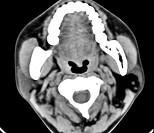

问题 女性,50岁,左侧面部肿胀,CT检查如图,应考虑为()

选项 A.左侧腮腺囊腺瘤 B.左侧腮腺囊肿 C.左侧腮腺脂肪瘤 D.左侧腮腺错构瘤 E.左侧腮腺炎

答案 C